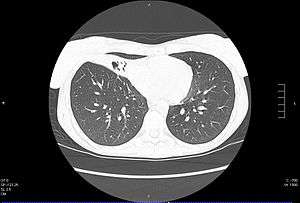

| CT scan of patient with right middle lobe aspiration and Mycobacterium avium infection consistent with Lady Windermere syndrome | |

- Chest X-ray or CT scan showing evidence of right middle lobe (or left lingular lobe) lung infection